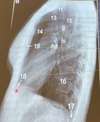

Que estructura anatómica esta en el numero 11

Traquea

41

Que estructura anatómica esta en el numero 13

Vasos supra aórticos

42

Que estructura anatómica esta en el numero 15

Espacio retro traqueal

43

Que estructura anatómica esta en el numero 9

Cayado aórtico

44

Que estructura anatómica esta en el numero 14

Espacio aéreo retro-esternal

45

Que estructura anatómica esta en el numero 19

Esternón

46